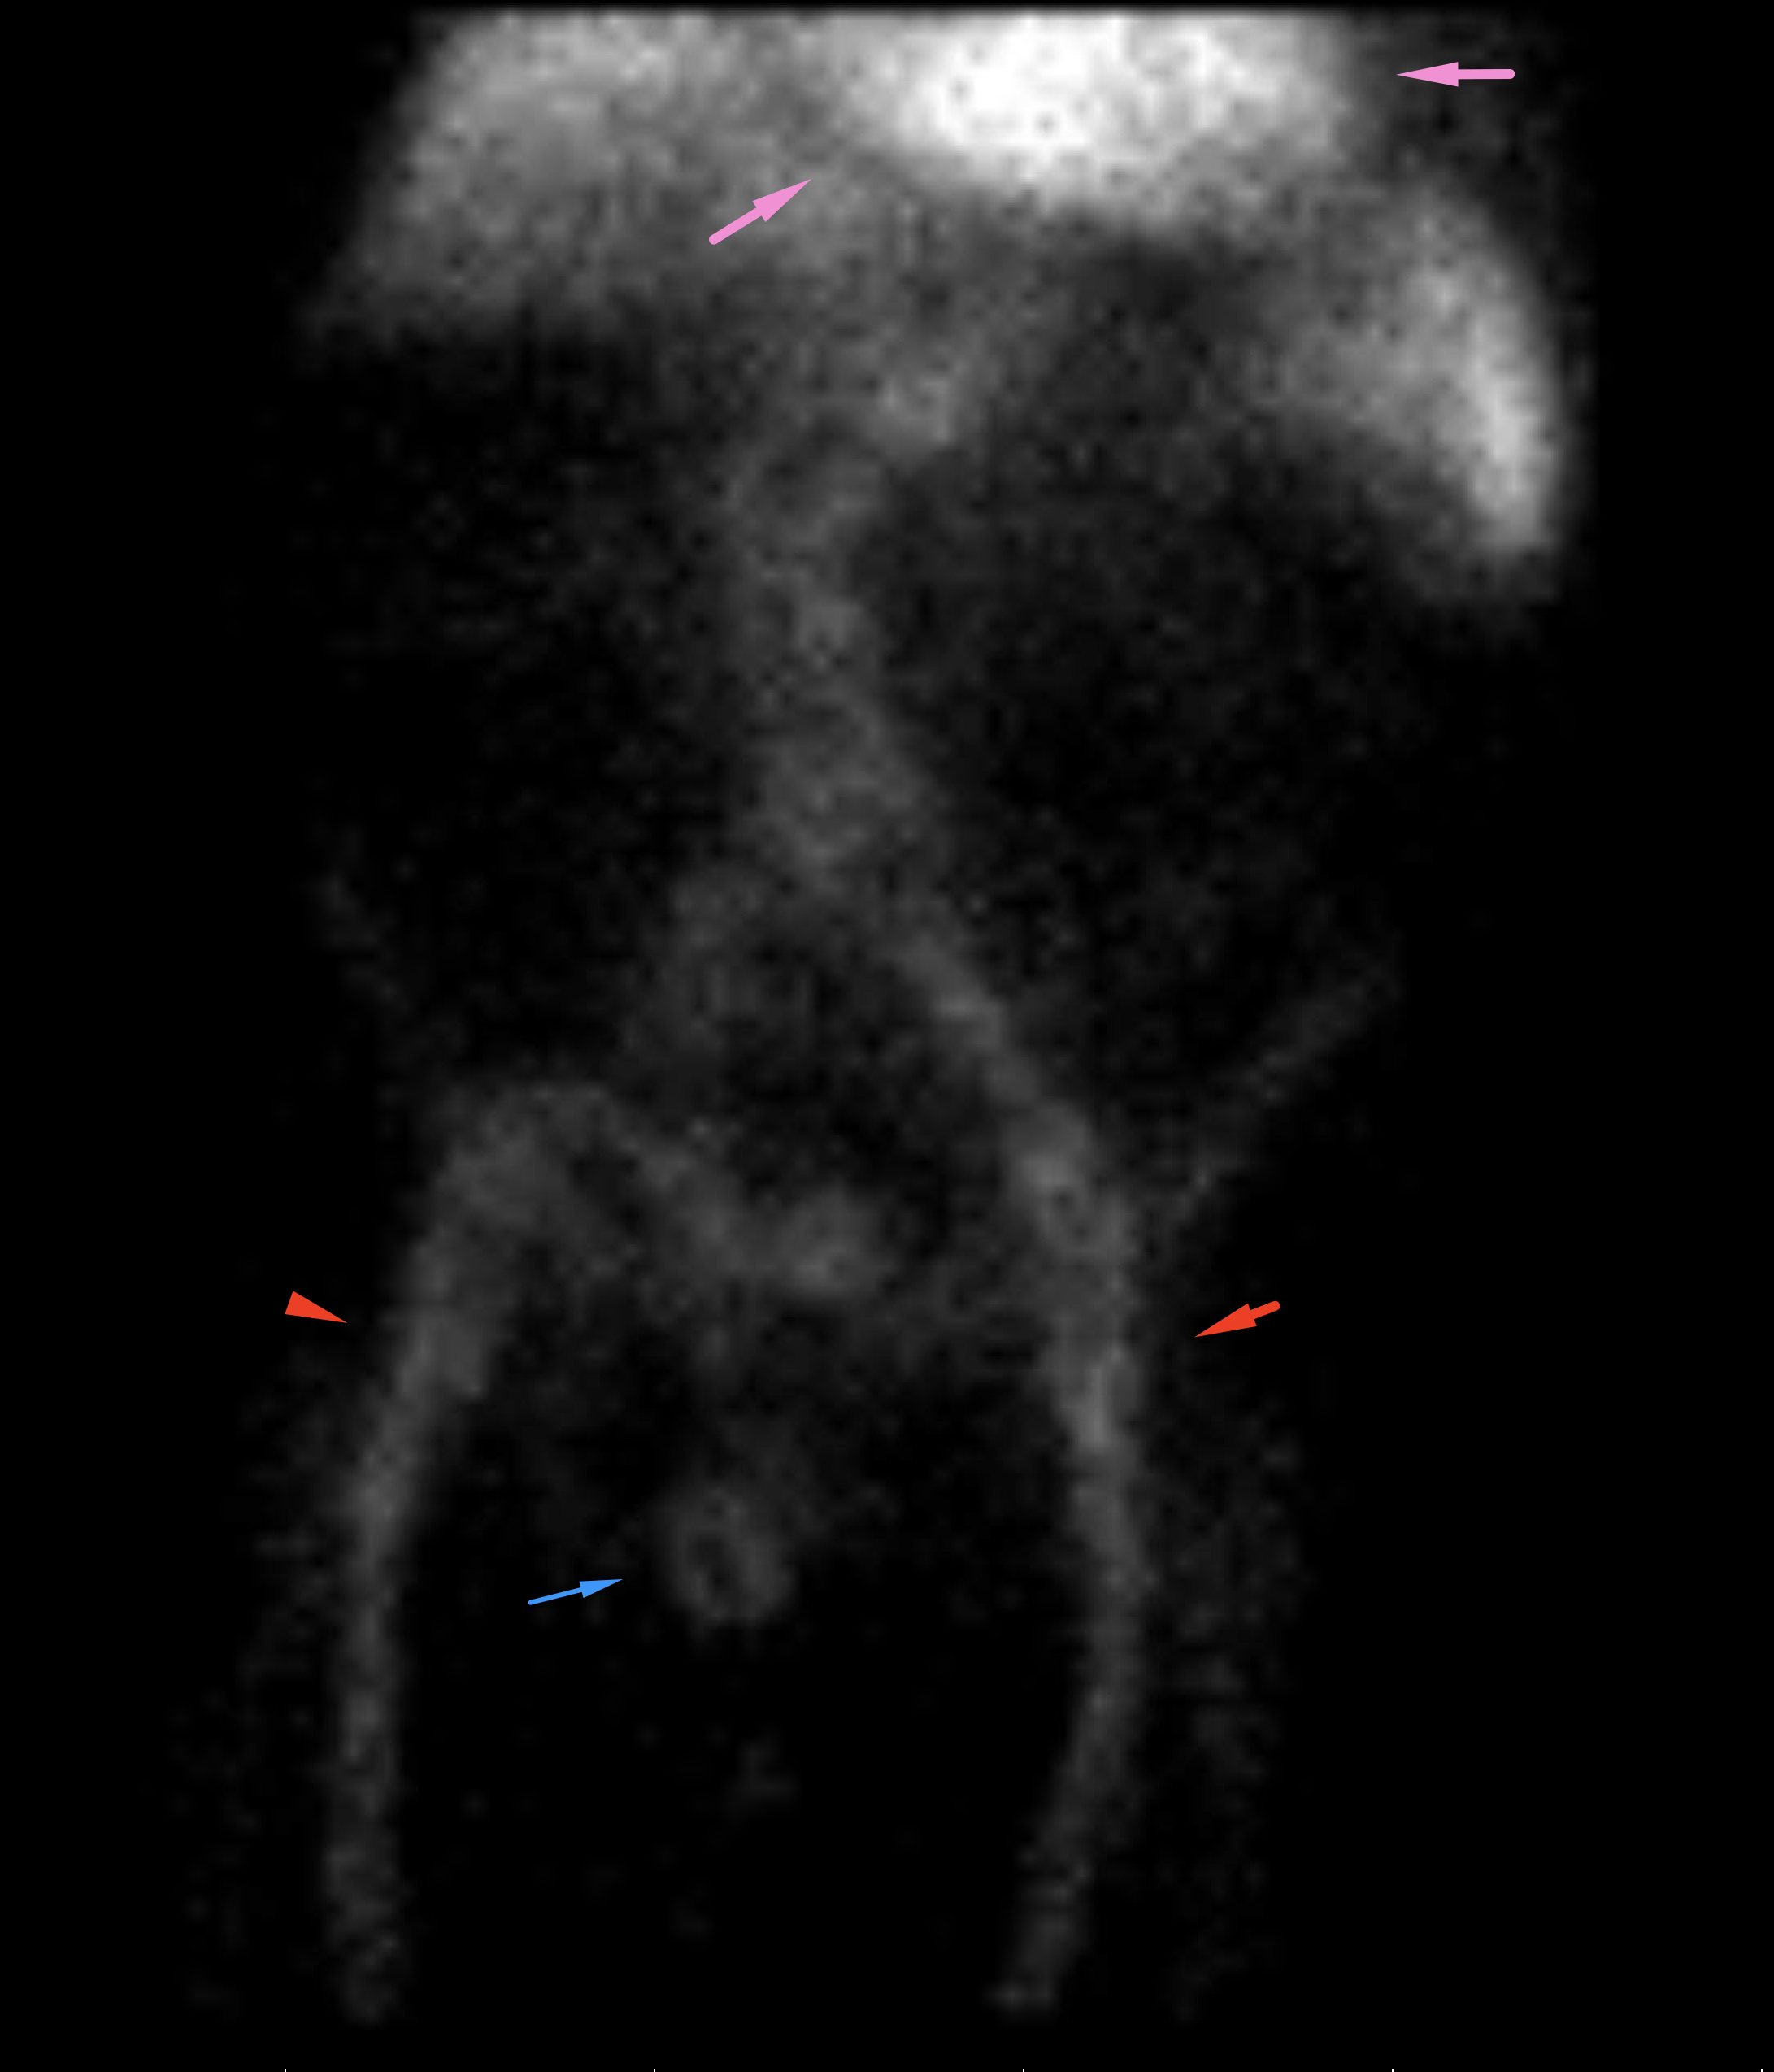

Age: 93

Sex: Male

Indication: Hematochezia

Radiotracer: Tc99m labeled RBCs

Sample ReportNo evidence of active GI bleeding during the course of this study.